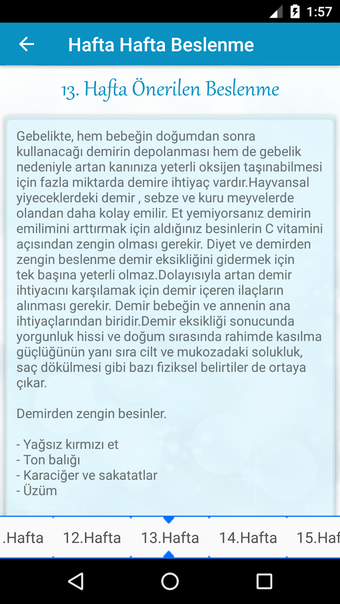

Hamilelik Takibi is an Android application created by HokkabazSoft that offers a simple and comprehensive way to track your pregnancy. It provides detailed information about each week of pregnancy and offers nutritional tips to ensure a healthy pregnancy. You can also track your baby's height and weight, watch videos of the baby in the womb, and ask and answer questions on a platform for other users. With the aid of specialists, the Hamilelik Takibi app has collated women's accounts of their 40-week pregnancies. You may view an ultrasound or 3D drawings of your developing child every week and receive weekly updates on their progress. Monthly updates for the next 9 months are also shown for your perusal. The information in the app has been compiled from many sources (including the internet and professionals) and is provided to you as an average. Therefore, it is suggested that you do not follow the advice in the application without visiting your doctor since it may not give you the real values of your kid. In sum, Hamilelik Takibi is a powerful tool for monitoring pregnancy and learning how to have a healthy baby.